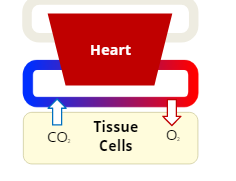

Internal Respiration

the exchange of the gases, oxygen and carbon dioxide, between the bloodstream and cells in the body's tissues

Oxygenation

the process of supplying oxygen to the body’s tissue cells